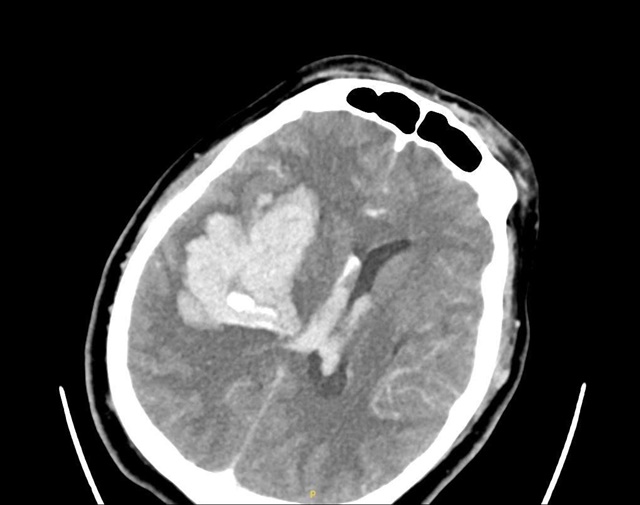

Kết quả chụp CT não tại bệnh viện cho thấy ông V. bị xuất huyết não diện rộng. Bệnh nhân được chỉ định đặt nội khí quản để bảo vệ đường thở và chuyển thẳng lên phòng mổ cấp cứu. Trong quá trình đặt ống nội khí quản, các bác sĩ đã hút ra một lượng lớn nước cốt chanh cùng với cặn thuốc đọng lại trong họng bệnh nhân. Bác sĩ xác định chính hành động cho bệnh nhân uống chanh, thuốc và chất lỏng của người nhà đã khiến chúng trào ngược vào đường thở, làm tình trạng suy hô hấp của người bệnh trở nên nguy kịch nhanh hơn. Sau một ngày cấp cứu tích cực, bệnh nhân vẫn phải nằm hồi sức.

Hình ảnh phim chụp bệnh nhân bị xuất huyết não lượng lớn bán cầu phải.